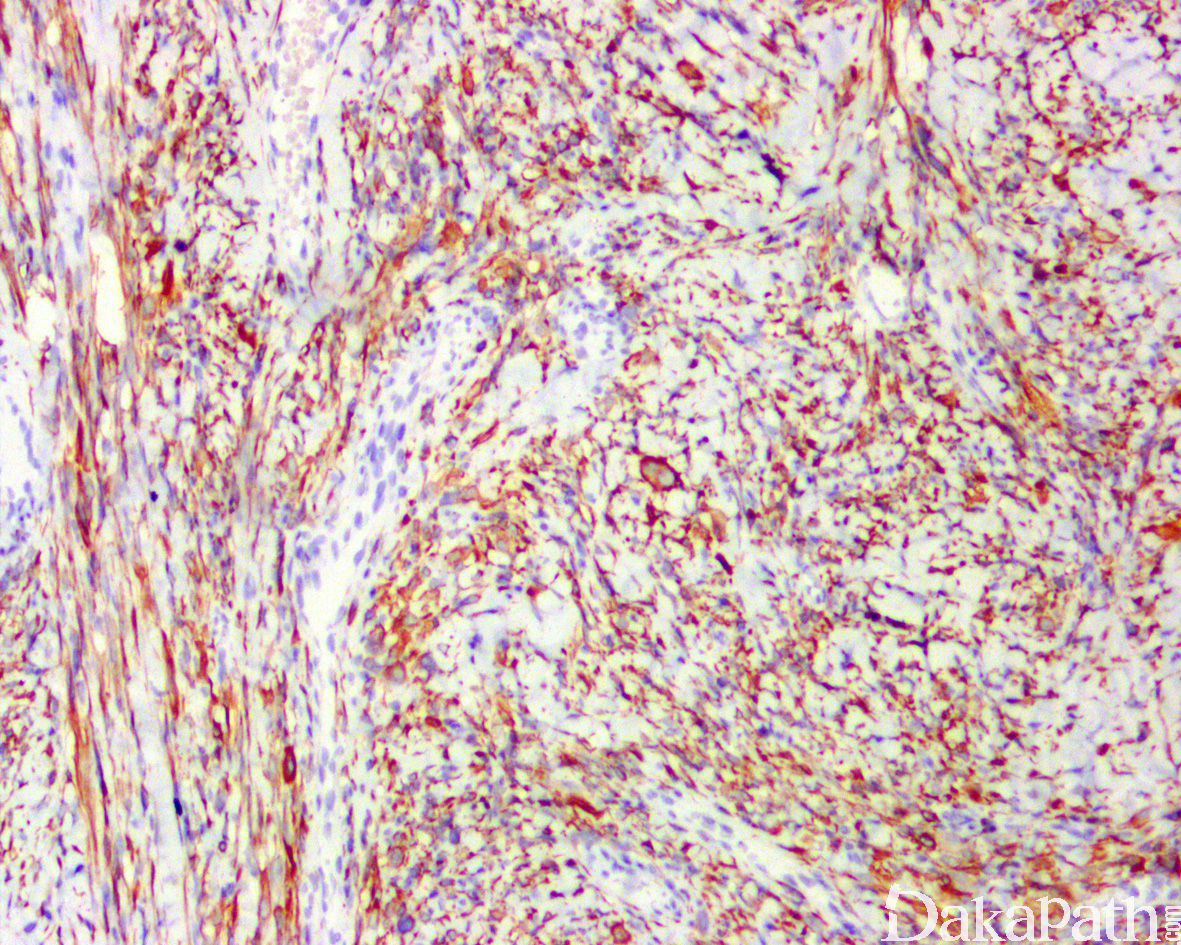

免疫组织化学染色:

MSA、desmin、myogenin 和 MyoD 1 阳性,可表达 CD56